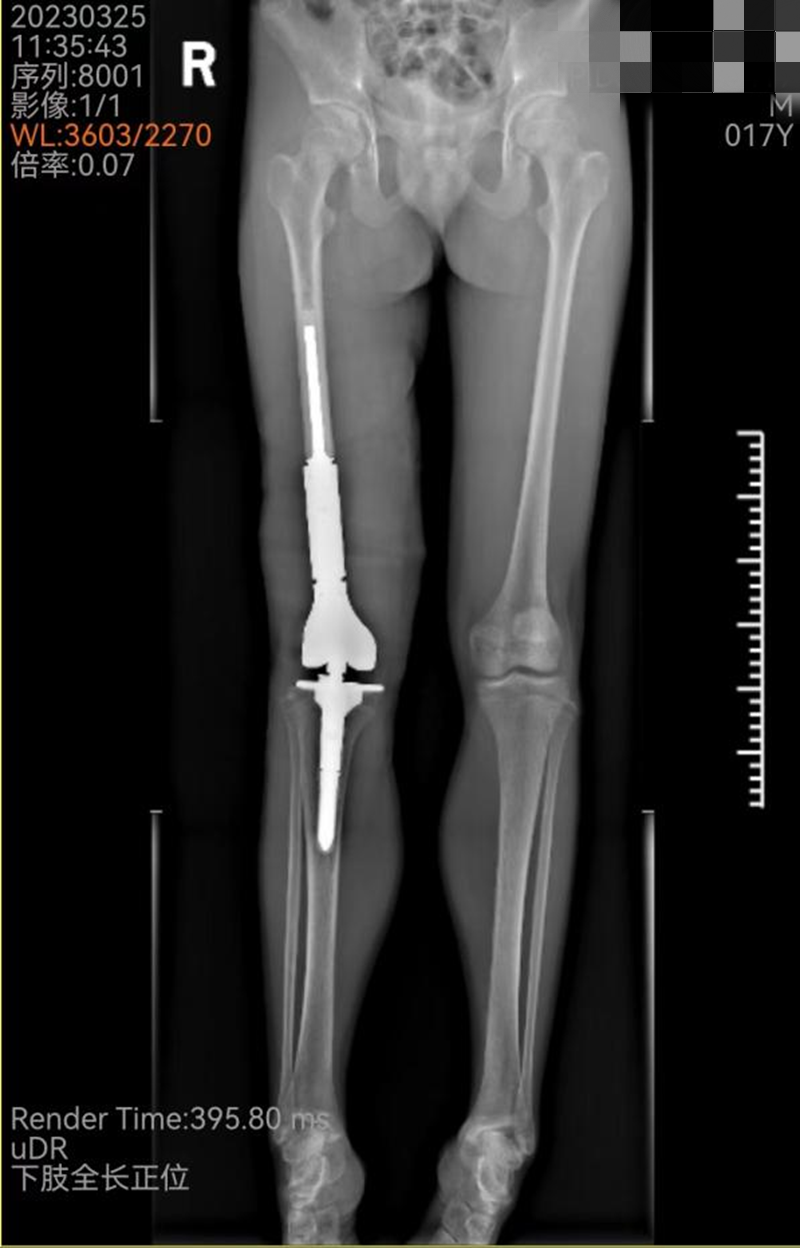

患者小王,17岁,因右大腿肿痛10个月不能行走,确诊为“右大腿股骨骨肉瘤”。入院后,骨科主任、关节外科病区主任、主任医师吴军团队结合患者肢体“病变范围发展快、范围大,靠近膝关节”的特点,为其制定了“先放化疗,再手术,再规范化疗”的治疗方案,在肿瘤科协作下,患者完成放化疗疗程后转骨科关节外科病区手术。放化疗后,尽管小王肿瘤有缩小,但肿瘤仍然侵及整个股骨下端、股骨髁和股中间肌,关节结构破坏严重。经过反复比对、测量,并利用电脑模拟切除肿瘤后关节重建范围等术前准备,吴军团队凭借娴熟和丰富的综合骨科经验,在完整保留股内外侧肌、股直肌、股骨近端、胫骨平台和神经血管的基础上,完整切除波及股骨及关节的肿瘤,按术前规划成功实施了股骨下段和膝关节的假体置换和重建。

手术完美重建股骨、膝关节

术后能自由行走